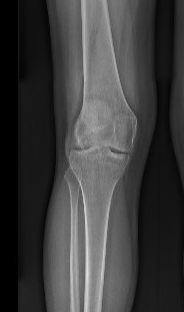

AP full length standing xrays

Line from centre of talus to desired mechanical axis

Line from centre of femoral head to desired mechanical axis

a) is the desired angle of correction